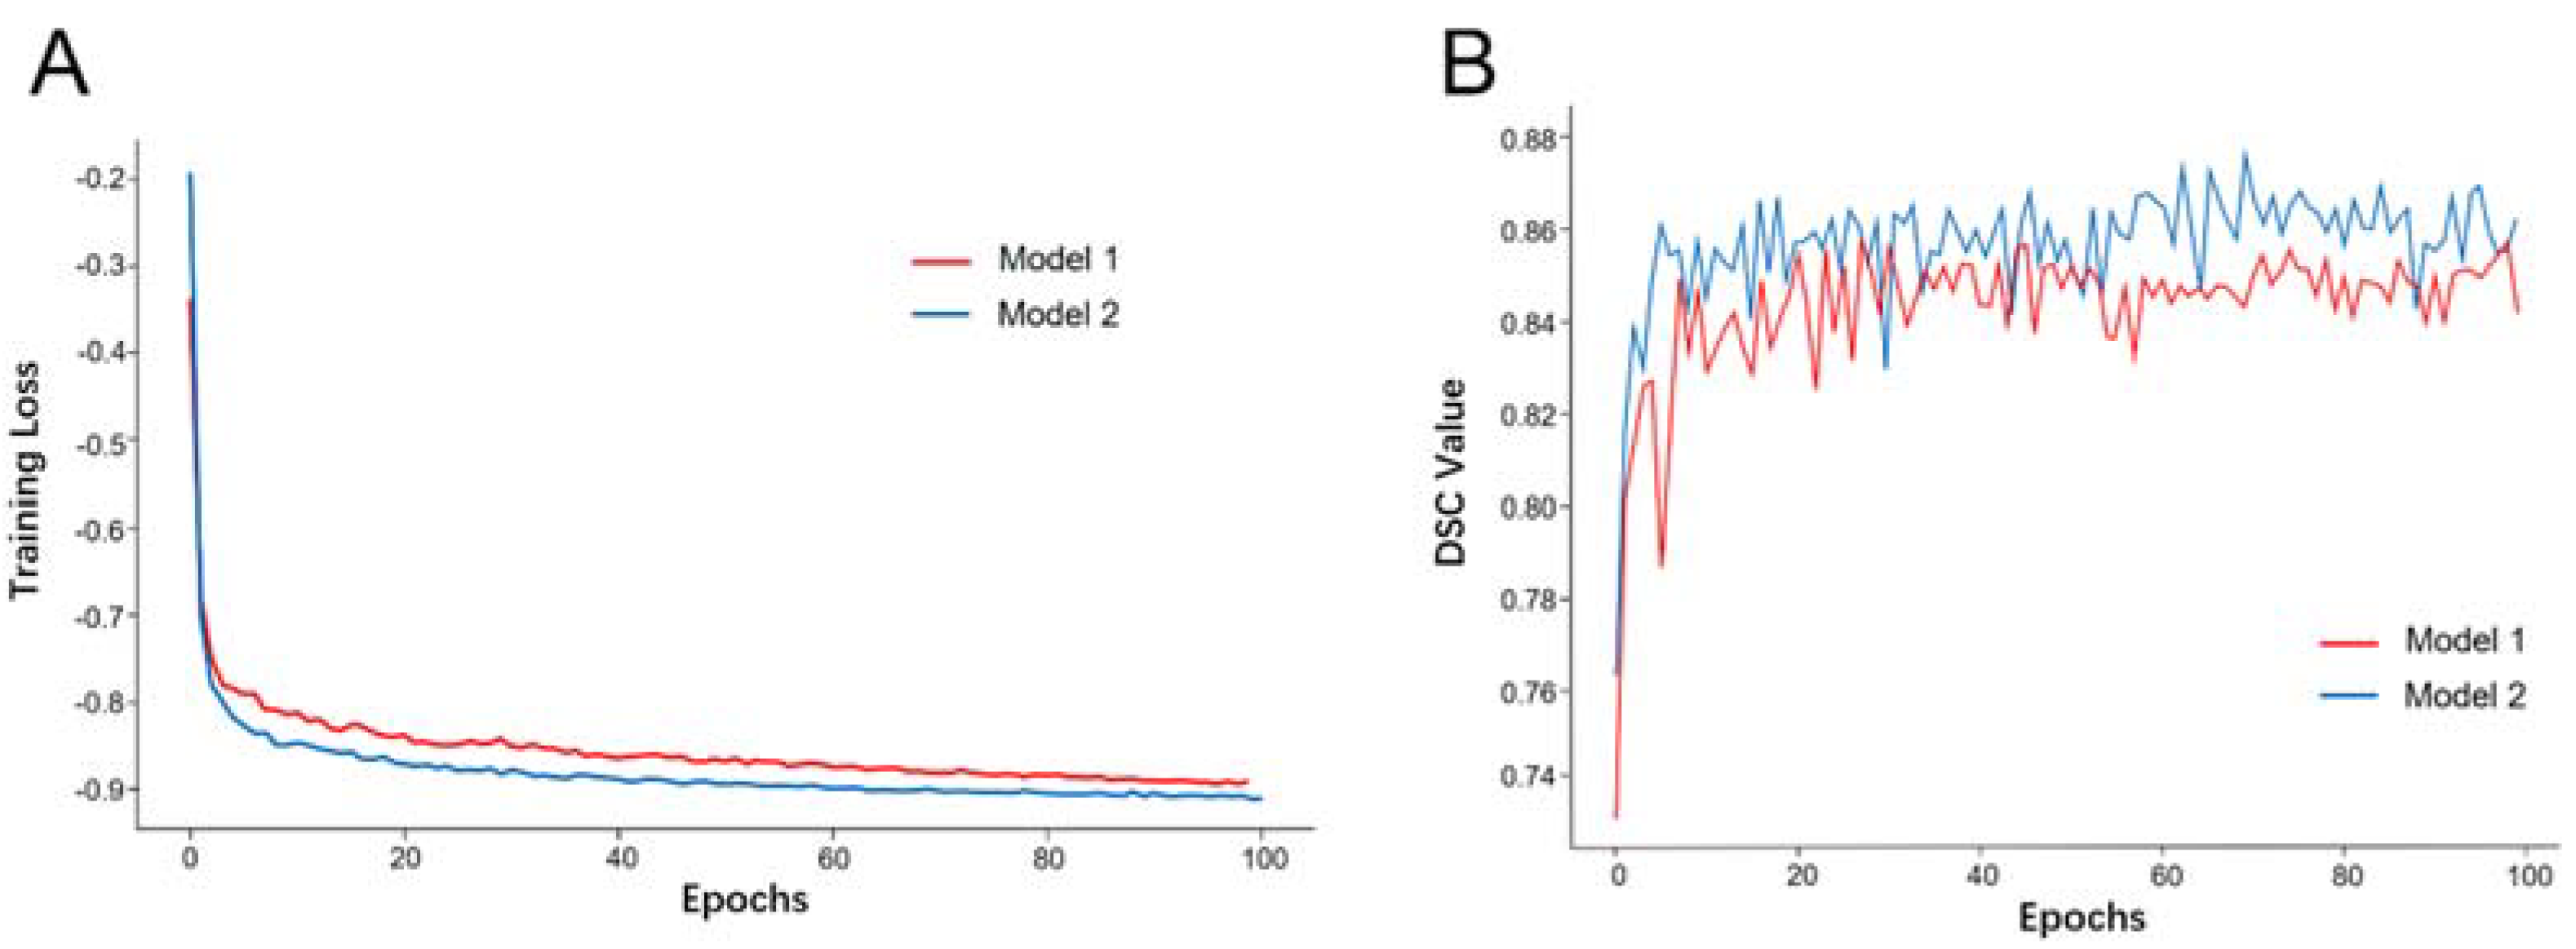

3.2. Model Training and Evaluation

3.3. Model Performance in the Validation Dataset

3.4. Model Performance in the Testing Dataset